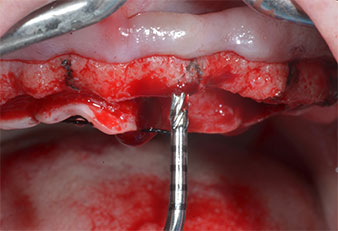

Un insert piézoélectrique diamanté de forme effilée (Piezomed I1) a été utilisé pour marquer les positions implantaires et effectuer la préparation pilote (Fig. 3). On a pris soin de travailler selon un mouvement ascendant et descendant, à puissance réduite, irrigation complète et basse pression (moins de 300g). Ensuite, un insert pilote (Piezomed I2A/I2P) a été utilisé pour l’agrandissement initial de 2mm du diamètre des sites implantaires (Fig. 4), suivi d’un insert de 3mm (Fig. 5).